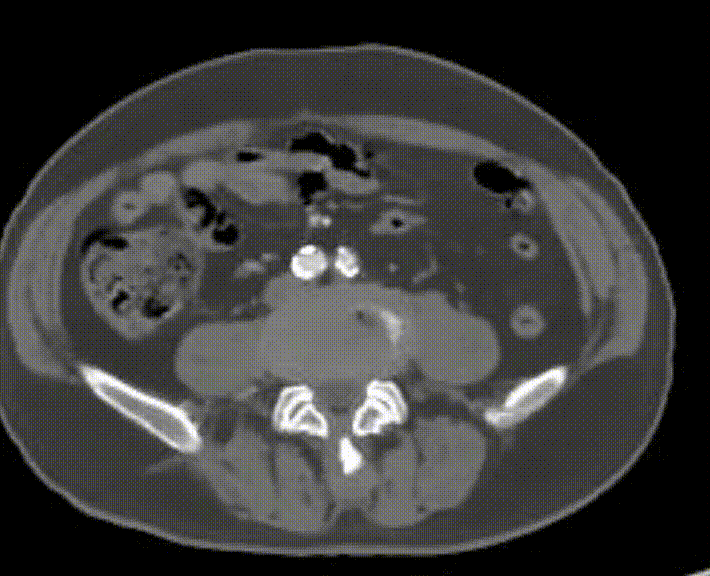

现病史:患者双下肢间歇性跛行5年余,跛距300米。后跛行症状加重伴双足发凉发麻跛距缩短至50米,右侧重、无静息痛、溃疡。下肢CTA提示:双侧股浅动脉重度狭窄近闭塞、右侧腘动脉重度狭窄

股浅动脉重度狭窄伴环周钙化

经导丝送入IVUS导管,股浅动脉近段重度狭窄、钙化明显,狭窄率大于90%

股浅动脉中远段及腘动脉重度狭窄、环周钙化明显